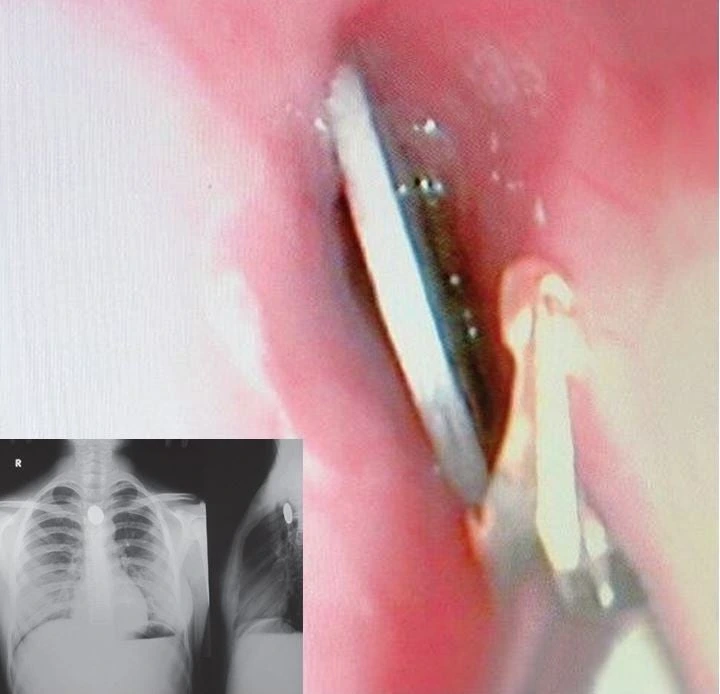

그거 말고는 애기들이 동전 같은 걸 삼켜서 목에 걸려 빼는 경우가 많죠.

귀에 비비탄을 넣어서 빼려고 어떻게 할까 고민하거나,

코에 콩알이나 장난감을 넣어서 어떻게 뺄지 고민하는 경우도 많아요.

그런 경우, 면봉에 순간접착제를 살짝 묻혀서

"잠깐만 있어봐" 하고 잡아서 붙인 다음 빼내는 방법을 쓰는 분도 있어요.

또, "마법의 키스" 방법이라 불리는 방법도 있어요.

애기에게 인공호흡하듯이 한쪽 코를 막고,

이물질이 있는 쪽 코를 열어둔 상태에서 턱을 들어주고,

입으로 후 하고 불어주는 거죠.

이렇게 하면 애기 코에서 "푹!" 하고 이물질이 나오는 경우가 있어요.

그래서 이런 방법을 부모님들에게 알려주곤 합니다.

- 2세 남아가 100원짜리 동전을 삼켜 응급실에 내원[6]

- 자석을 삼켜 내시경적 이물제거술 시행[6]

- 전신마취 하에 내시경적 이물제거술 시행[6]

- 겸자, 그물망 등을 이용해 이물 제거[18]

- 식도에 걸린 경우 즉각 제거 필요[12]